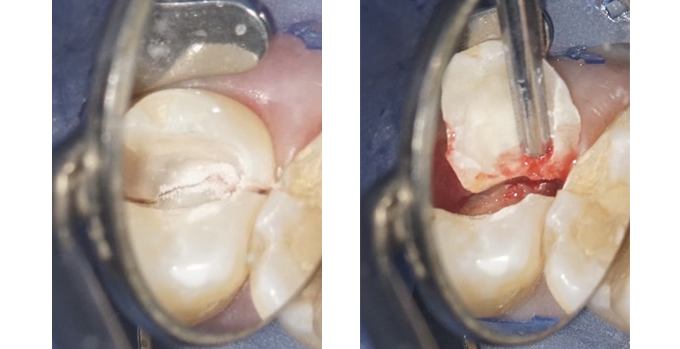

状態を確認すると歯が真っ二つに割れていて、

歯ぐきが化膿してました。

結局、割れた歯は抜かなくてはなりませんでした。

原因は、歯ぎしり・かみしめによる歯の破折と

そこへ細菌が入ったために起きた急性の炎症でした。